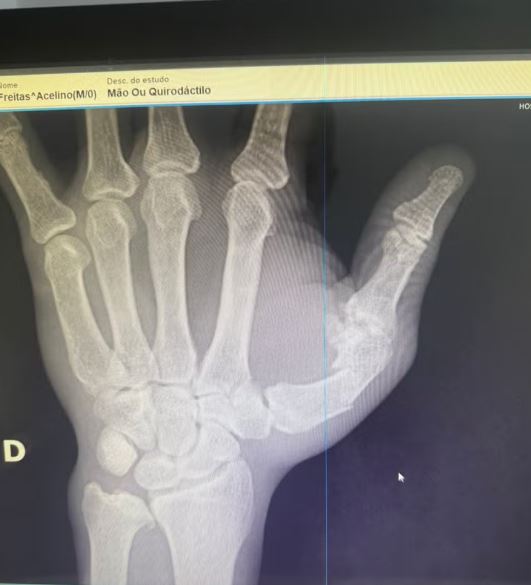

Uma imagem do Raio-X da mão foi divulgada pela assessoria confirmando a quebra.

A confusão começou logo após a desclassificação de Wanderlei por três cabeçadas ilegais no quarto round de um duelo previsto para oito. Equipes invadiram o ringue, e o filho de Popó, Rafael, acertou um soco que derrubou o paranaense desacordado por quatro minutos. Uma imagem do Raio-X da mão foi divulgada pela assessoria confirmando a quebra, fato inédito na carreira de 35 anos do atleta.